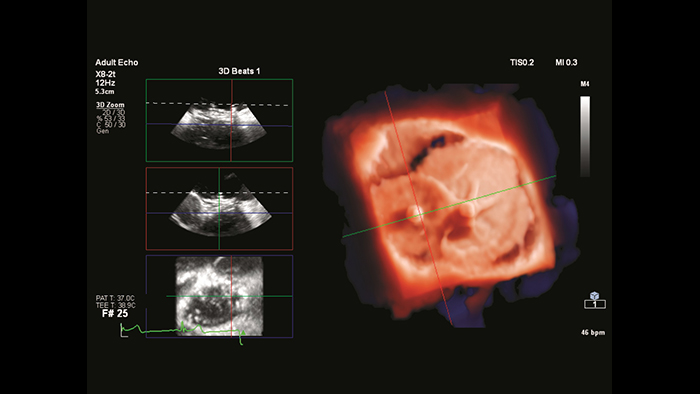

Segmentação do modelo cardíaco EchoNavigator

Fecho de ASD com fusão em tempo real EchoNavigator